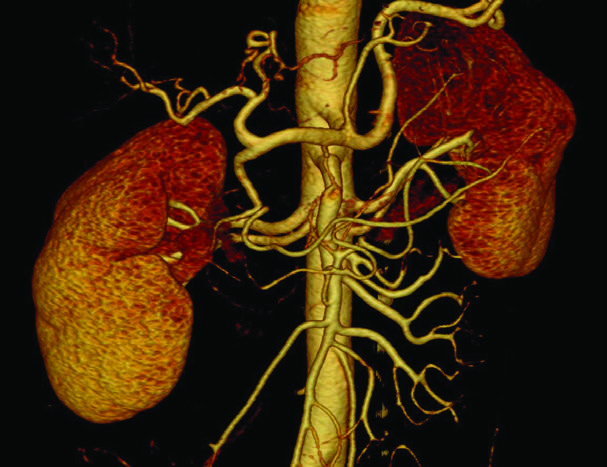

3D- реконструкция при исследовании мочевыделительной и дыхательной систем

Нужно отметить, что 3D реконструкция при исследовании мочевыделительной системы возможна только при в/в контрастировании и она не является в данных исследования…